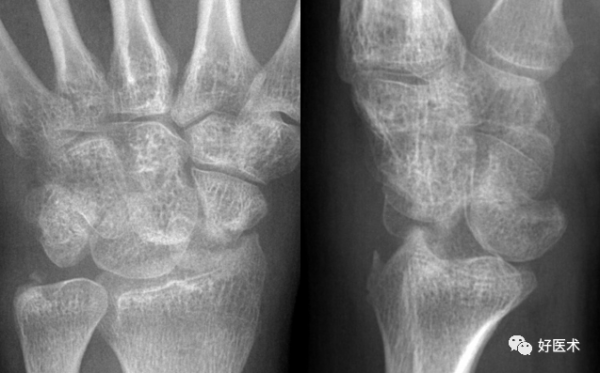

成人期腕關節正側位及舟骨蝶位片

1.舟骨 2.月骨 3.三角骨 4.豆狀骨 5.大多角骨 6.小多角骨 7.頭狀骨 8.鉤骨 9.橈骨莖突 10.尺骨莖突 11.第一掌骨基部

12.舟骨結節 黑箭:舟骨腰部 白箭:舟骨滋養血管影